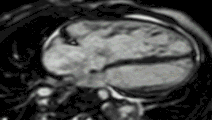

Late gadolinium enhancement

Gadolinium-based contrast agents are administered intravenously and delayed imaging is performed at least 10 minutes later to achieve optimum contrast between normal and infarcted myocardium. An inversion recovery (IR) sequence is used to null the signal from normal myocardium. Myocardial viability can be assessed by the degree of transmural enhancement. Cardiomyopathic, inflammatory and infiltrative diseases may also have distinctive patterns of non-ischemic LGE.[21][22]